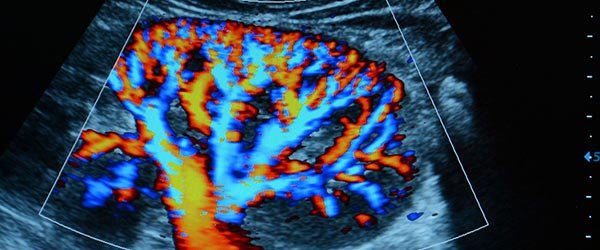

Ultrassonografia com Doppler

Quando o exame é realizado com Doppler, além das imagens anatômicas, é possível avaliar o fluxo sanguíneo das artérias e veias, detectando possíveis alterações circulatórias, como:

- Obstruções vasculares

- Tromboses

- Aneurismas

- Problemas cardíacos

- Varizes

Essa análise detalhada é fundamental no acompanhamento de diversas patologias vasculares e no planejamento de tratamentos.